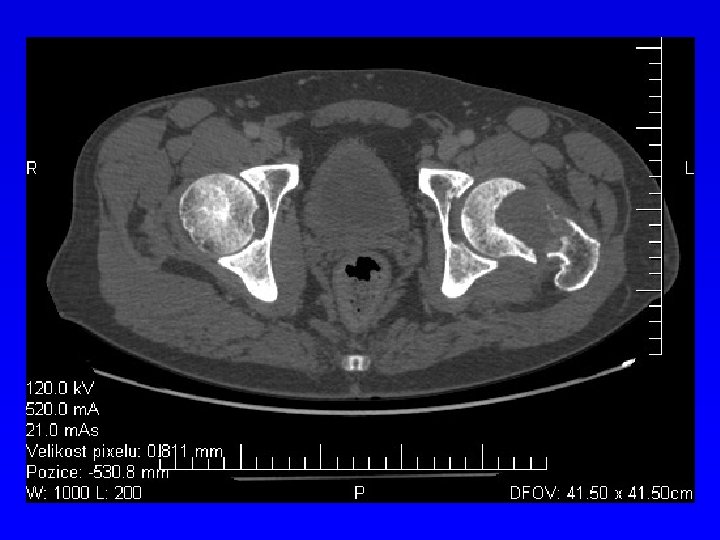

Výpočetní tomografie CT Absorpce RTG záření ve tkáních Fotony se přěměňují na el. impulsy Ty se převádí do digitální podoby Tkáňová denzita – odstíny šedi Vzduch – 1000 H. U. Voda 0 H. U. Kost + 1000 H. U. Kontrastní látky- enhancement Onemocnění kostí Nádory kostí a kloubů

CT